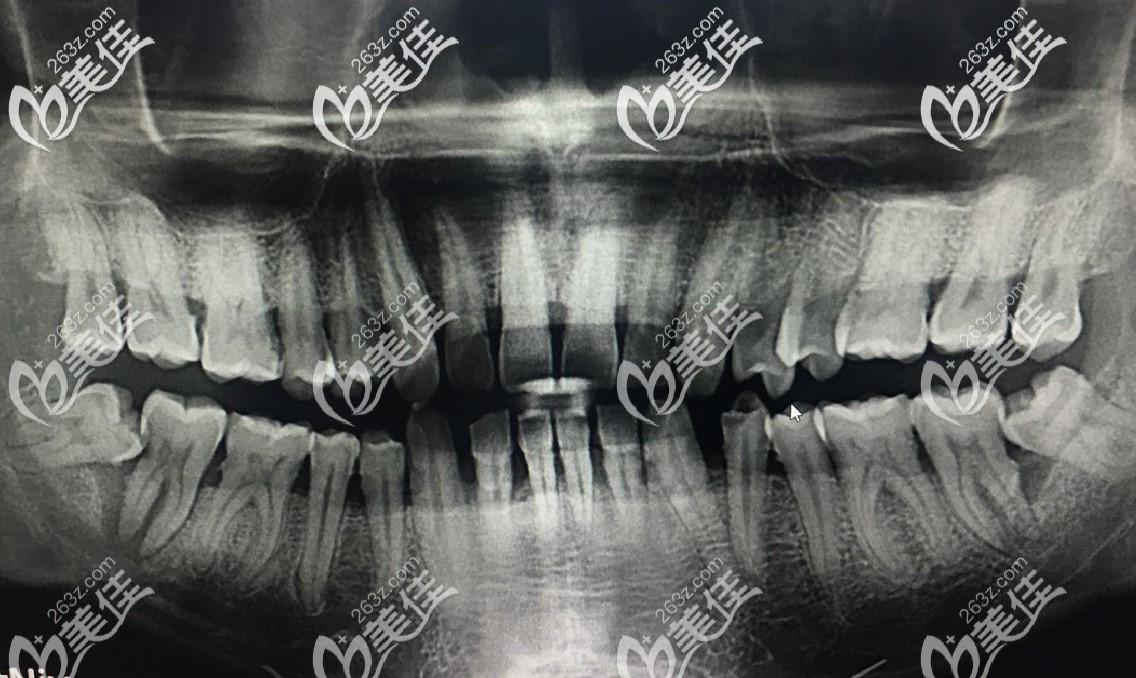

牙齿刚开始疼的时候没在意,疫情期间在家疼的我坐立难安,好不容易等到口腔医院开门,去检查,医生说是横生智齿导致的,拍片后发现,我的第二磨牙也被智齿顶了个洞。

拔掉智齿之后,医生说,我的挨着智齿的那个大牙坏的比较厉害,已经伤到了神经(自己吃东西的时候,冷了热了都感觉疼的难受)。并且第二磨牙还松动,如果治疗价值不大,建议拔掉做种植牙。